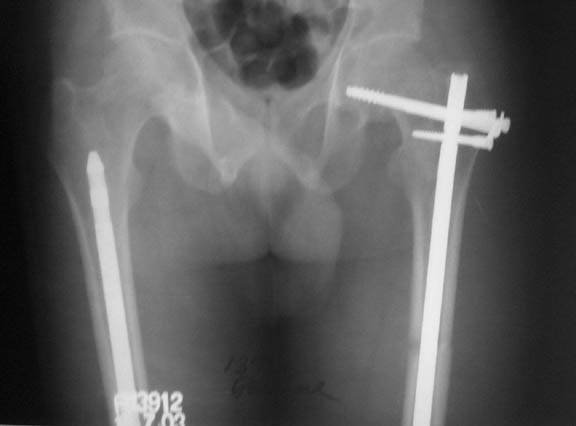

We managed to get neutral phosphate, initiated medical treatment and did an antegrade SIGN nailing of left femur along with couple of screws to neck using miss a nail technique. He complained of pain of the right femur and both forearms. In OT these areas were screened using image intensifier and found that he has looser zones of all these with impending fractures. Yesterday we did a retrograde nailing of right femur usingSIGN nail. Both ulnas were stabilised usingLambrudini wires in a closed fashion. All fractures and looser zones were stabilised by closed surgery using image intensifier. It may be interesting to see the post of picture of both the hips in which one side shows an antegrade femoral SIGN nail and the other side shows a retrograde SIGN nail.